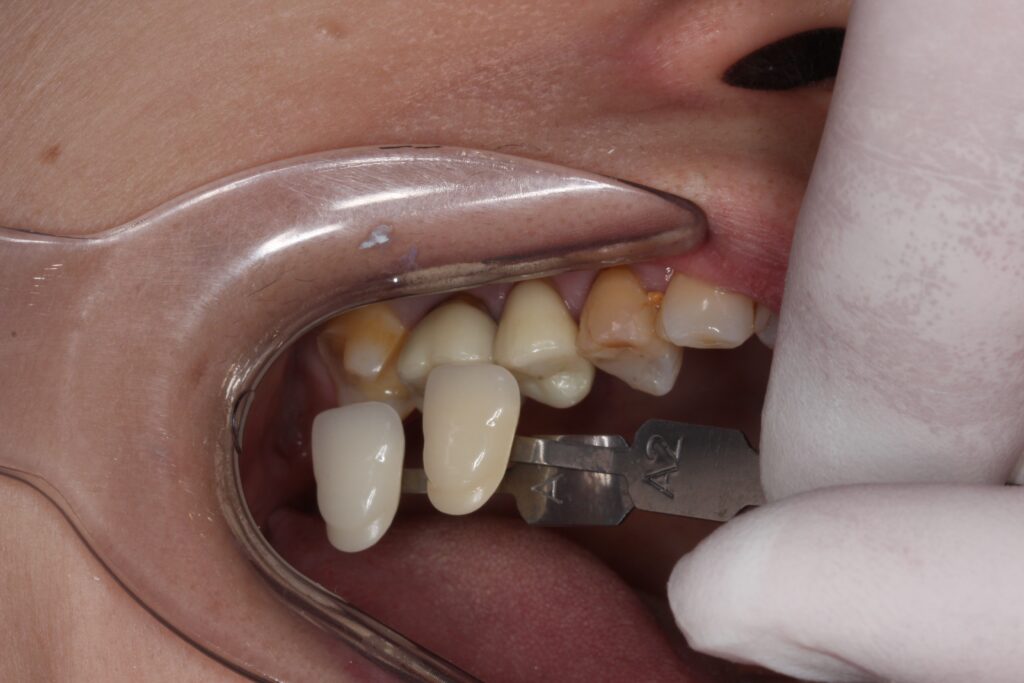

歯型を取ってセラミックインレーを製作します。

歯の色を記録して、歯科技工士がその方に合った歯を製作します。

セラミックインレーがセットされた状態です。

どこを治療したのか分からないくらい綺麗に仕上がりました(^^)/

自然な色でセットされています。

手前の歯のジルコニアクラウンの不自然な白い色が目立ちますね。